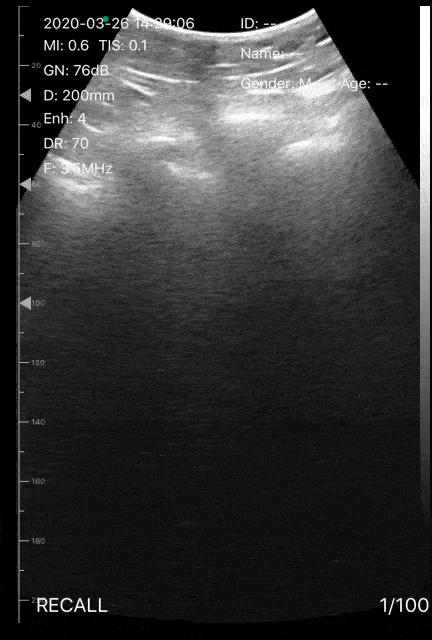

This lung ultrasound illustrates a small subpleural consolidation with associated waterfall b-lines in a patient with suspected COVID-19. The patient was a male in his mid 30s who presented to the ED with cough, but no fever. On admission the patient had an O2 saturation of 85%, with no respiratory distress. Image courtesy of Dr. Victor Bang (@vmjbang) Co-Founder of Pocus Jedi